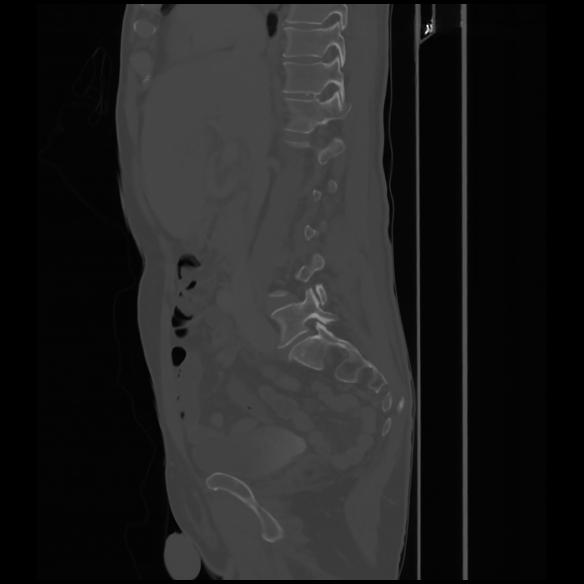

7 CUERPO,CE,Sagittal,3.000,CUERPO,Sagittal,